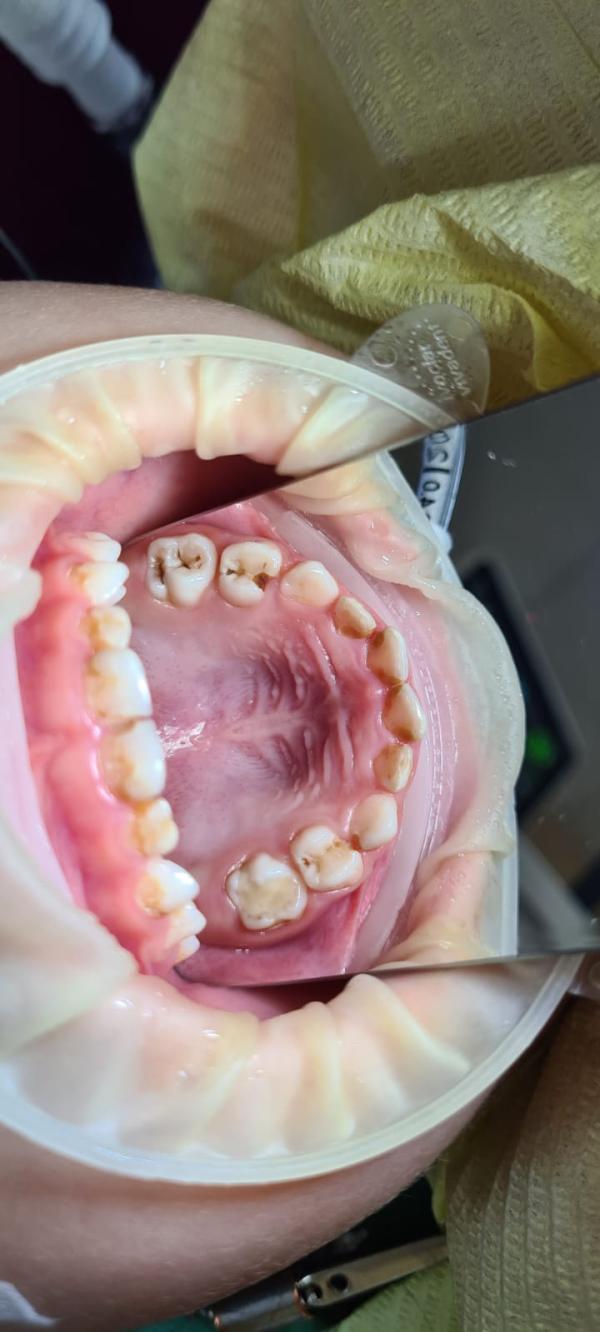

Наш врач Филиппов Григорий, астынныбыт аган от проделанной работы. Все вышло на 128тысяч, рассчитывали на 118. Ынырык астыктыктык онордо все зубы😍

Вуаааа,9 тииспитин кариес булбуттара бугун☹️аюая..Отостом чо то отзыв плохие ди сорохторго туьэн хаалар диэн ,ТТТ боюсь